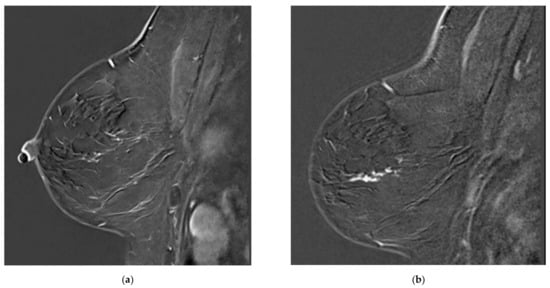

Breast lesions were first classified according to whether or not they were missed. The missed lesions were defined as visible on MR A (as a mass, non-mass enhancement, or focus standing out from background parenchymal enhancement) (Figure 1). The so-called missed lesions were subdivided into two categories, namely either overlooked, i.e., not described in the initial radiology report of MR A, or misinterpreted, either expressed as BI-RADS 2 or BI-RADS 3 on MR A, subsequently becoming BI-RADS 4 or BI-RADS 5 on MR B (Figure 1 and Figure 2). Non-missed lesions were defined as the absence of mass or non-mass enhancement on MR A. For each lesion, the MRI characteristics were documented according to the BI-RADS lexicon (T2 signal, size/volume, margins, distribution, enhancement and kinetics).

Figure 2. Overlooked segmental non-mass enhancement: (a) MR A; (b) MR B; (c) MR B MIP showing the enhancement standing out from BPE, corresponding to high-grade DCIS.